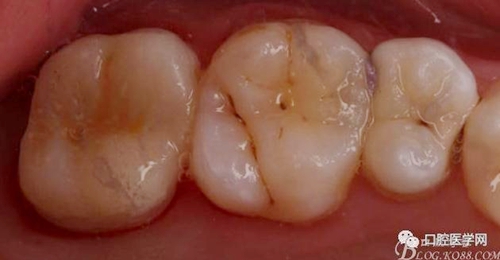

排齦后樹脂充填,高嵌體制備

取模后用樹脂自行高嵌體制作,咬合通過對合調(diào)整,領(lǐng)面用彈性樹脂去除法調(diào)整,有些照片未拍攝

口內(nèi)粘接完成,幾乎無調(diào)整,就位完全,咬合良好

口內(nèi)檢查咬合,情況良好。